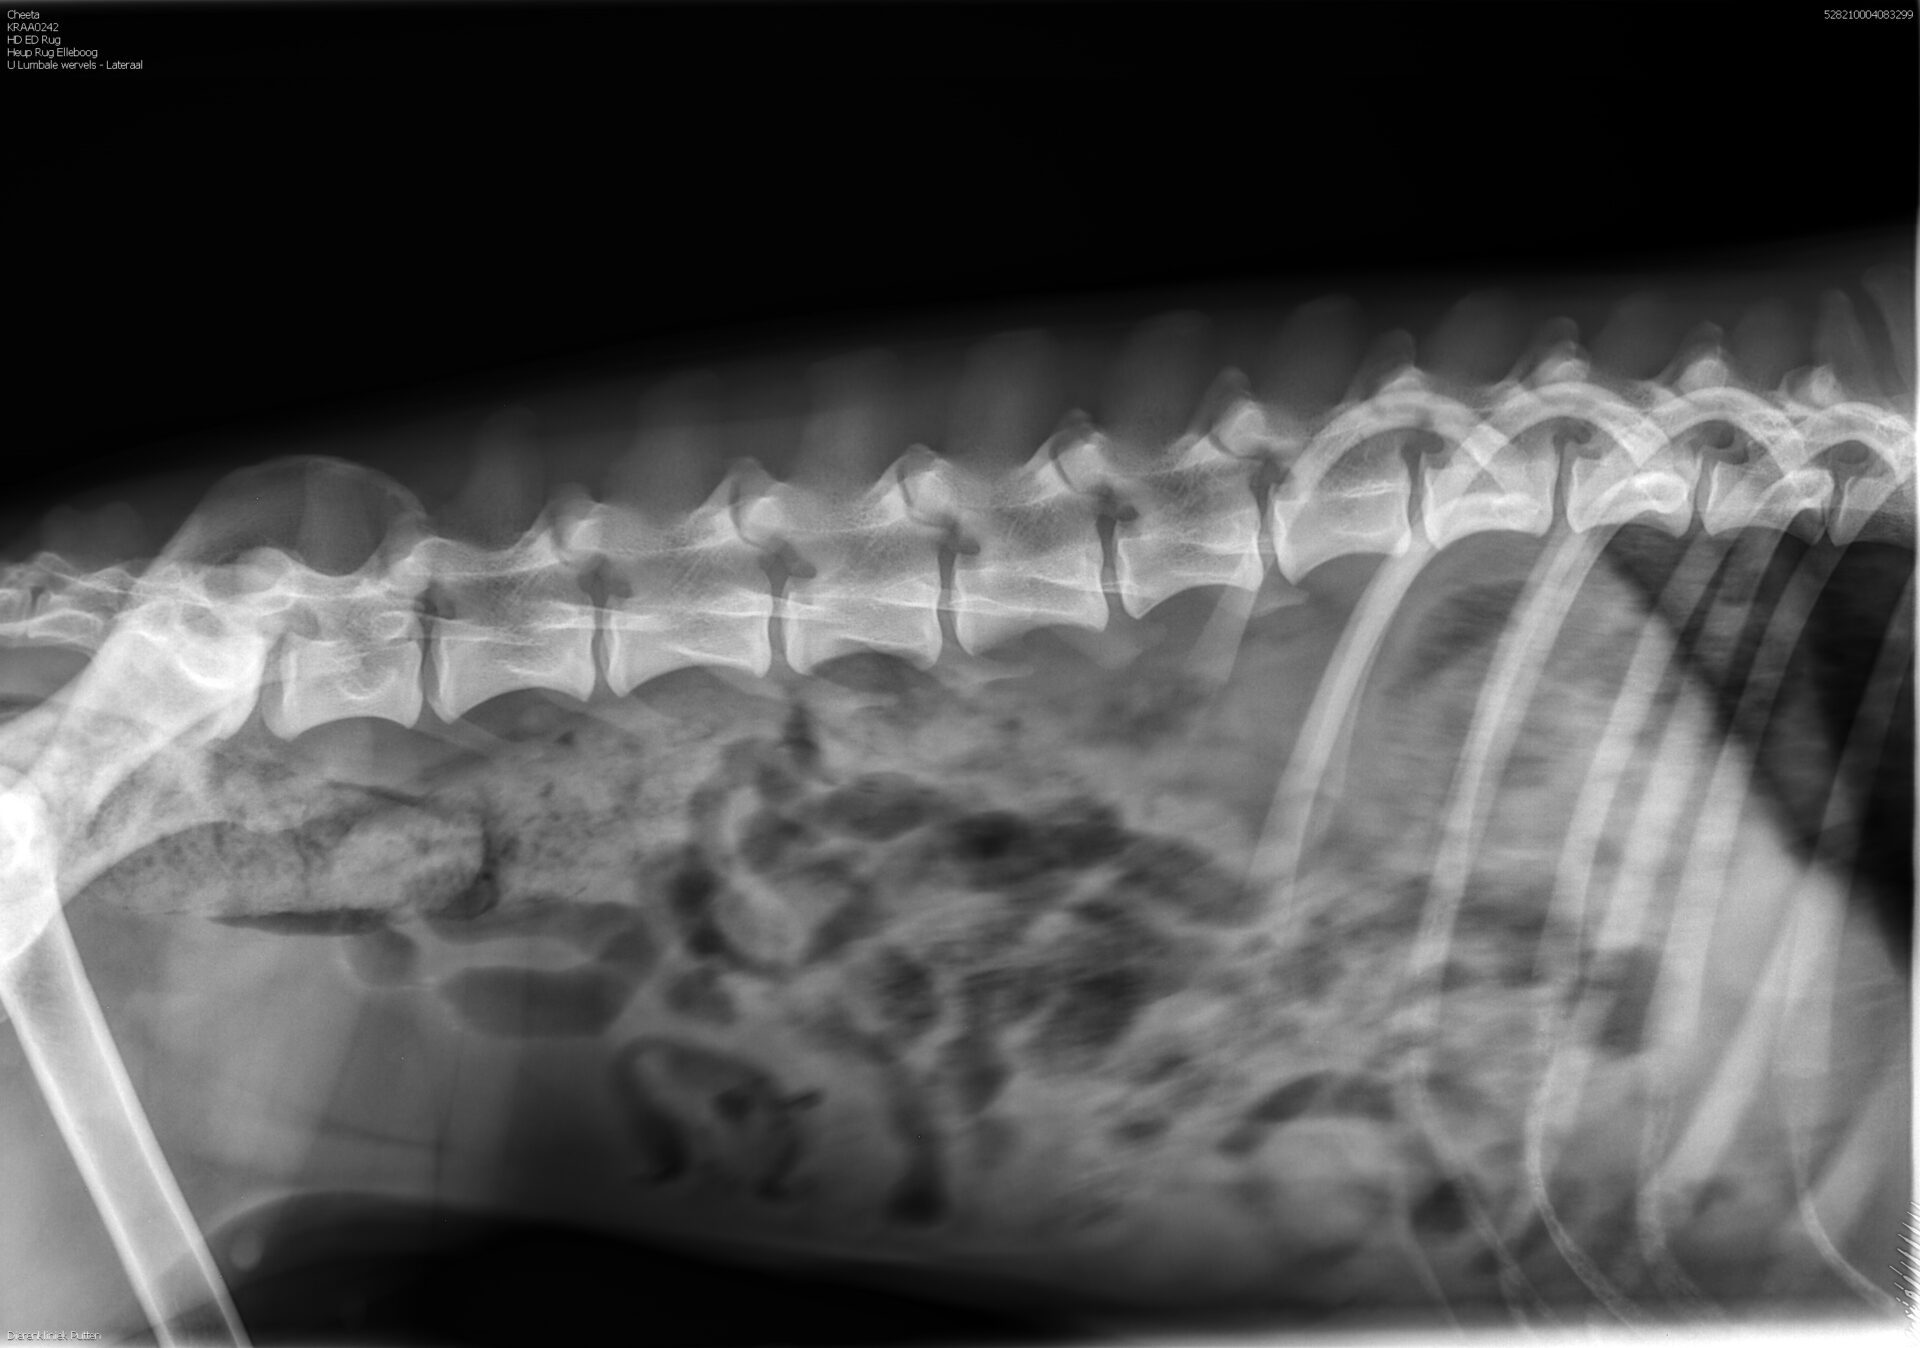

rug: 100% (foto’s aanwezig)